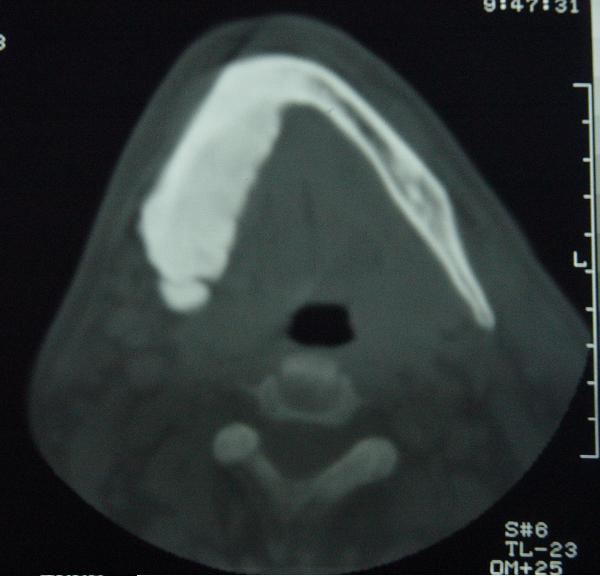

标题: CT12465:下颌骨肿瘤,请会诊 [打印本页]

标题: CT12465:下颌骨肿瘤,请会诊

发现下颌骨肿瘤近30年.逐渐增大.

考虑右侧下颌骨水平部及升部骨纤维异常增殖症可能性大。

考虑右侧下颌骨骨化性纤维瘤。